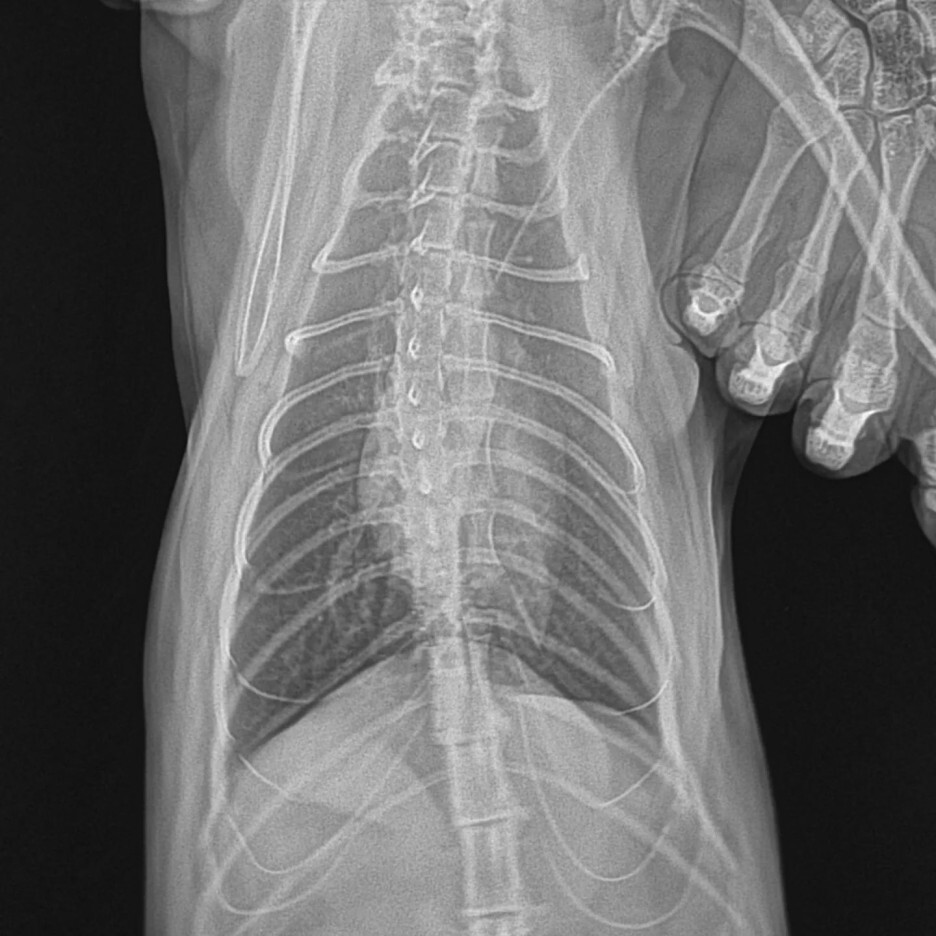

엑스레이를 무려 4번을 찍고 나서야 또리 뒷 다리 골두가 깨졌음을 확인이 가능했습니다. ㅜ.ㅜ

이 엑스레이가 3번째였습니다.. 이때는 진통제를 먹어보고 똑같이 아프다고 보이면

꼭 다시 데려오라고 하셨습니다.. (동네동물병원이 아닌 2차 병원임)